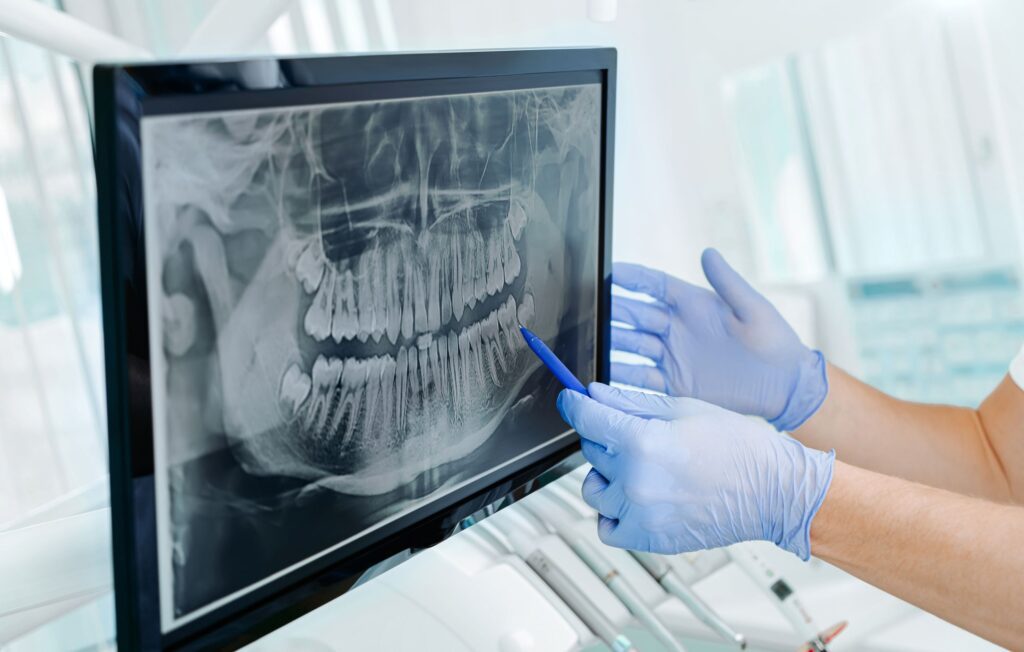

- Review: Once the images are taken, they are displayed instantly on a computer screen. Your dentist will review them with you, explaining any findings and answering your questions. Digital X-rays make it easy to zoom in and highlight specific areas, so you can clearly see what’s happening inside your mouth.